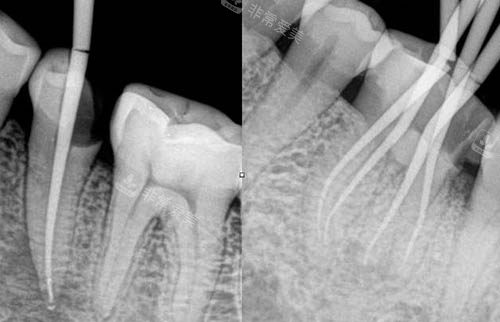

根管治疗动画演示

正在进行根管治疗的牙齿

根管治疗后的牙齿

根管治疗ct照片